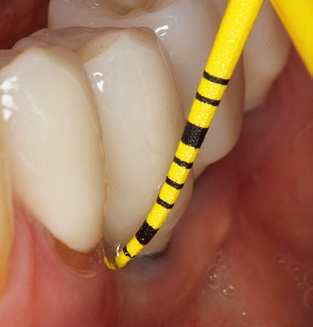

Das aktuelle Arbeitskonzept für die UPT

Die Aktualisierung der Anamnese stellt im Rahmen der UPT eine zentrale Maßnahme dar, sie sollte mindestens einmal jährlich erfolgen. Sie dient dazu, mögliche neue Risikofaktoren zu erkennen und zu dokumentieren. Vor allem dann, wenn ein Patient langjährig betreut wird, ist es wichtig, zu erfahren, ob sich patientenspezifische und allgemeinmedizinische Risikofaktoren verändert haben. Hier sollte an erster Stelle an ein erhöhtes Risiko durch Diabetes gedacht werden, aber auch andere allgemeinmedizinische Erkrankungen (kardiovaskuläre Erkrankungen und Neoplasien) können aufgrund der erfolgten Therapien und der notwendigen Medikamenteneinnahme zu einem veränderten Risikoprofil führen. Das Update der Anamnese ist also auch im Rahmen der UPT sehr wichtig, um gegebenenfalls aufgrund eines veränderten Risikoprofils eine Veränderung des Behandlungsintervalls zu veranlassen. Im nächsten Schritt ist es wichtig, der Diagnostik besondere Aufmerksamkeit zu schenken. Die Instrumentation ist zwar ein zentraler Bestandteil der UPT, in keinem Fall sollte sie aber Bestandsaufnahme und Dokumentation verdrängen. Für die Diagnose ist dabei der parodontale Befund unerlässlich, eine Zunahme der Sondierungstiefen und eine Erhöhung des BOP­Index sind zentrale Indikatoren für eine Progression parodontaler und periimplantärer Erkrankungen. Zum Erheben der benötigten Daten darf daher nicht davor zurückgeschreckt werden, auch Implantate zu sondieren. Dabei ist es wichtig, dass hierfür millimeterskalierte PAR­Sonden verwendet werden. Für die Sondierungsbefunde an natürlichen Zähnen haben sich seit Jahrzehnten metallische Sonden bewährt. Bei Implantaten ist die Herausforderung für das Erheben korrekter und reproduzierbarer Sondierungsbefunde größer. Da es durch die Diskrepanz von Implantatdurchmesser und Kontur der Suprakonstruktion regelmäßig zu einer Überkonturierung der Suprastruktur kommt, sind für Sondierungen an Implantaten flexible, aber dennoch millimeterskalierte Son­ den sehr sinnvoll (z. B. Colorvue Kit PCV11KIT6, Hu­Friedy; Abb. 4).

Abb. 4: Für das Sondieren an dentalen Implantaten sind biegsame, millimeterskalierte Sonden empfehlenswert (z.B. Colorvue Kit PCV11KIT6, Hu-Friedy). – Abb. 5a und b: Eine gerade Arbeitsspitze (1P, W&H Dentalwerk Bürmoos GmbH) ist universell für die Instrumentierung natürlicher Zähne geeignet. – Abb. 6: Für die Bearbeitung schwer zugänglicher Bereiche der Zahn- und Wurzeloberflächen (z.B. Furkationen) bieten sich gebogene Arbeitsspitzen (3Pr/3Pl, W&H Dentalwerk Bürmoos GmbH) an. – Abb. 7: Die spitz zulaufende sechseckige Implantatreinigungsspitze (1I, W&H Dentalwerk Bürmoos GmbH) ermöglicht eine atraumatische und effiziente Reinigung der Kronen- und Abutmentoberflächen. – Abb. 8: Für die manuelle Instrumentierung der Implantatoberflächen sind Titan- oder Carbonküretten geeignet.